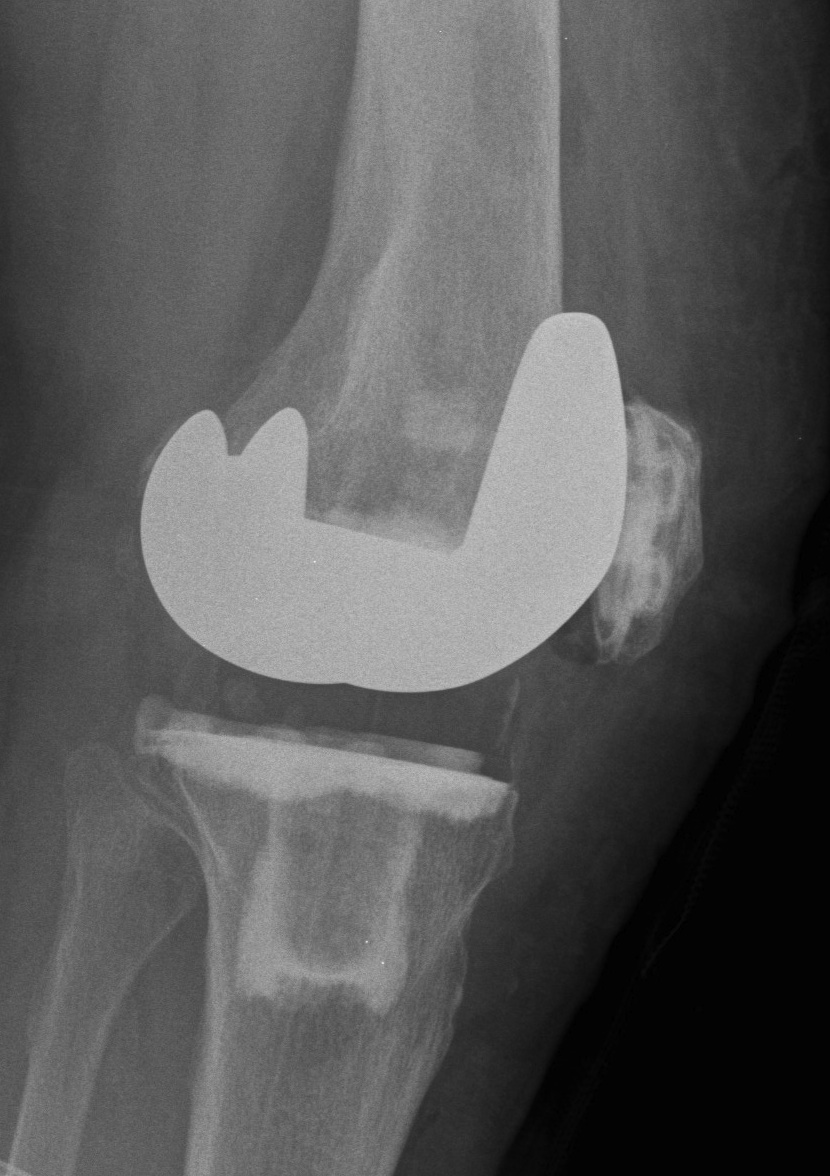

The ideal TKA maximises articular conformity while minimising axial constraint

Highly conforming / Fully congruent

- constant sagittal femoral radius

- large contact areas

- theoretical limitation of flexion to 120o due to posterior impingement of the tibial component

- low wear rates

- poor ROM

- may be improved by mobile bearing

Low conforming / Partially congruent

- large contact areas in the first 20o of flexion

- contact area decreases with flexion due to a decreasing sagittal radius

- improves flexion range

- good ROM

- higher wear rates